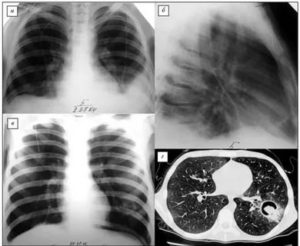

Метод рентгенографии легких применяют только при тяжелых формах патологии. Это позволяет выявить изменения бронхиального древа, плевры и тела легких, деформацию ребер.